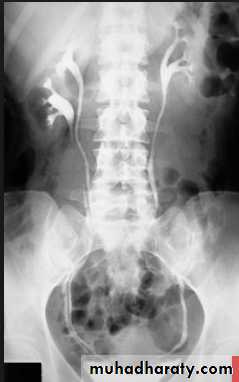

IVU

Large kidney .Lobulated out-line.

Distortion of pelvi- calyceal system depend on cyst size, number and position.

In advanced cases there is elongation and stretching of minor and major calyces ( spider leg).

In advanced cases IVU shows non-functioning kidney .